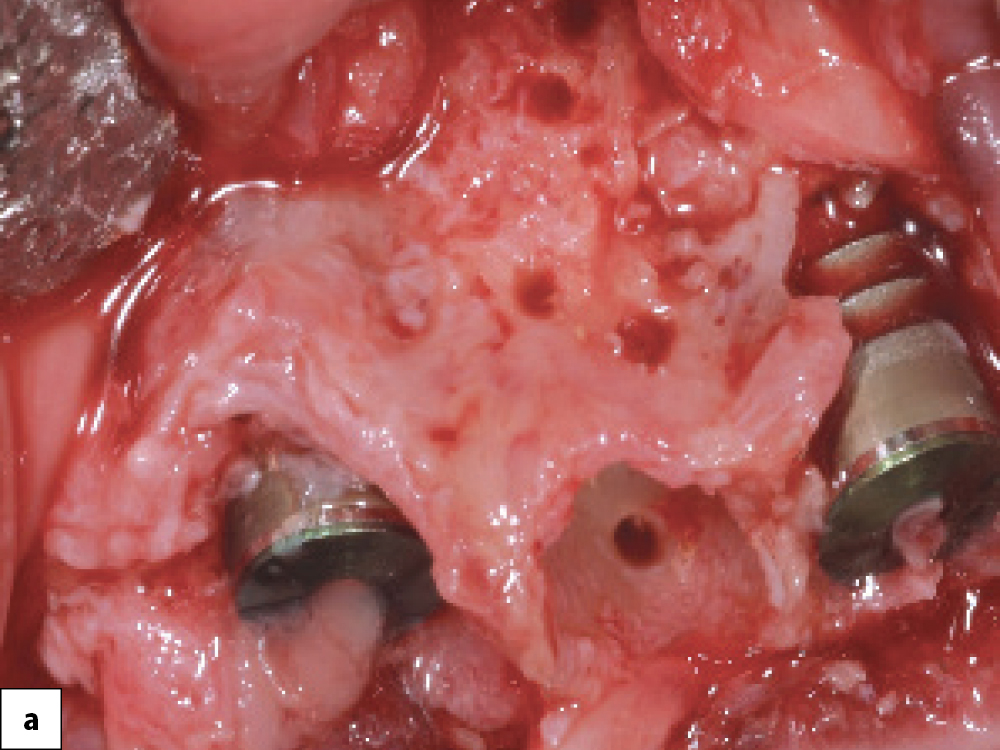

Bony Defect Evaluation A

Bony Defect Evaluation B

Bony Defect Evaluation C

Bony defect evaluation: (a) Flap reflection allows the clinician to visually evaluate the size and location of the fenestration to determine whether the defect will compromise implant positioning or primary stability when immediate implant placement is desired; (b) Examples of a large fenestration (green arrow) and loss of the buccal plate (blue arrow), either of which would contraindicate immediate implant placement due to the inability to obtain primary stability; (c) Additional example of flap reflection to show the fenestration.